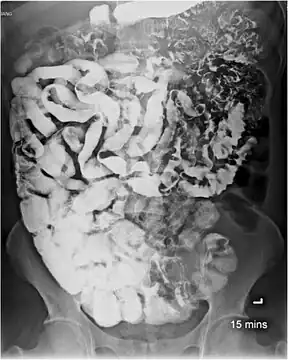

Intestinal capillariasis diagnosed by endoscopic biopsy. -

Small bowel study in intestinal capillariasis showing continuous long segment of fold thickening, fold effacement, and increased luminal fluid.[4]